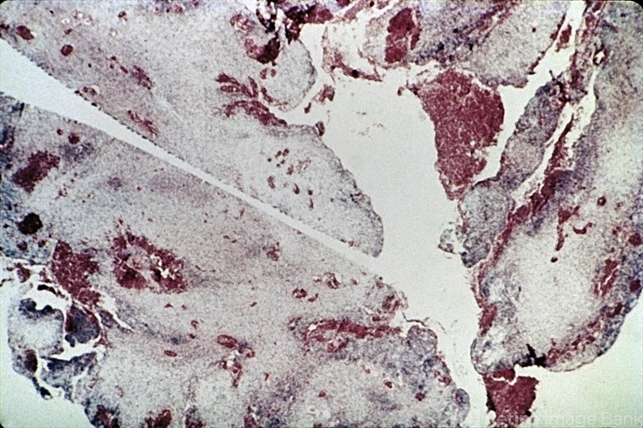

- Embryonal rhabdomyosarcoma. At low magnification, the tumor's embryonal character is apparent, with alternating dark, cellular areas and light, mucinous spaces (H&E xl6).